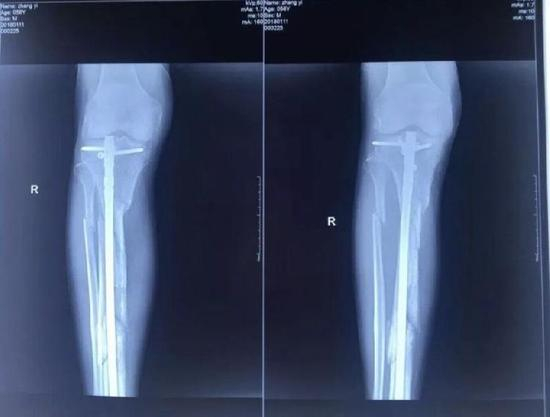

张毅被打的情况发生于2017年10月18日,在廊坊师范学院内,四名歹徒持镐把张毅打伤,致其右腿粉碎性骨折。